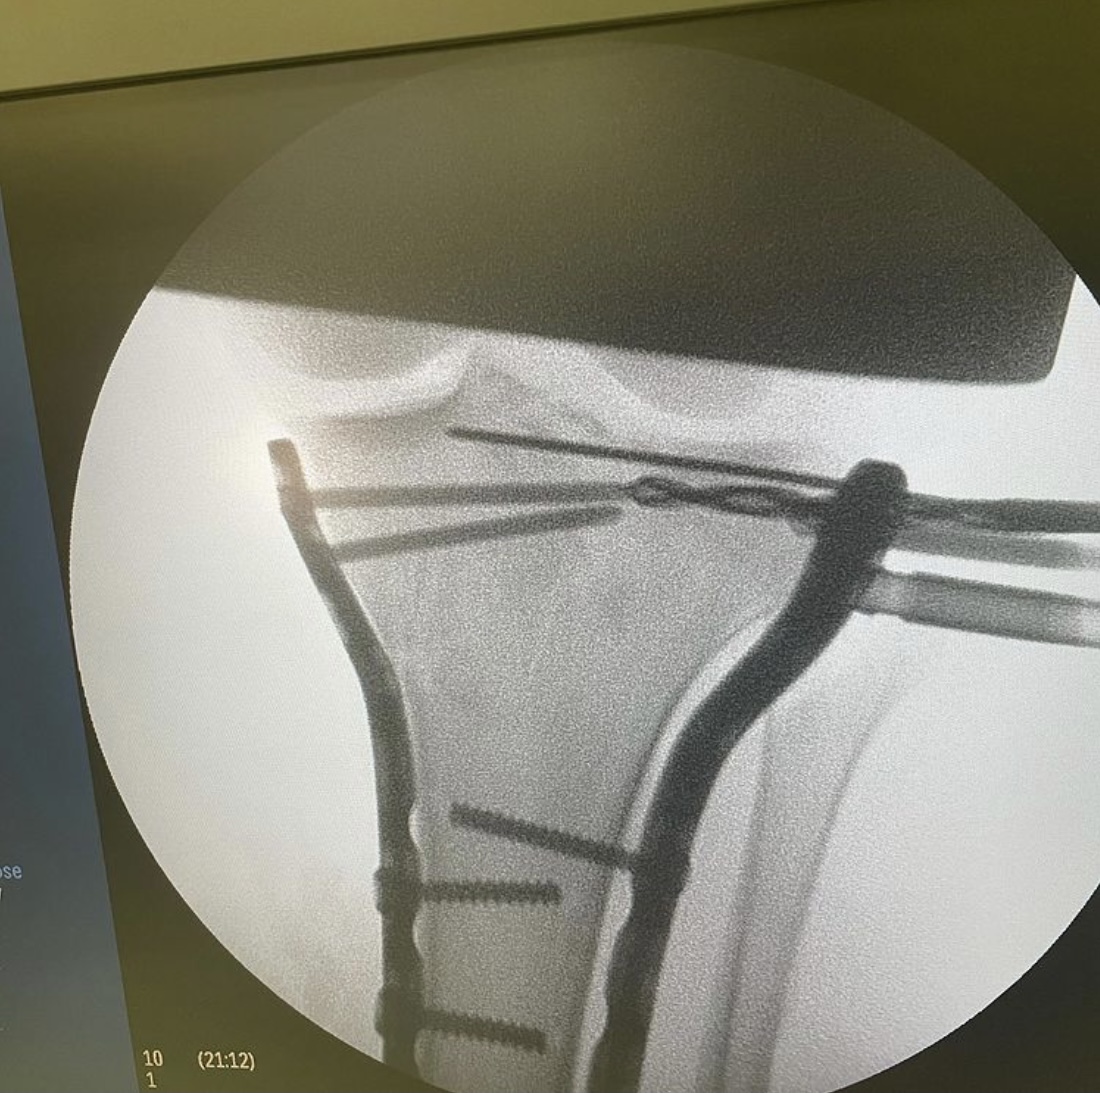

На операционном столе пациент с травмой в результате падения с самоката — многооскольчатый перелом верхнего суставного конца большеберцовой кости с разрывом боковых связок.

«Выполнен остеосинтез пластинами и винтами, восстановлены связки коленного сустава, — рассказывает хирург — травматолог ГКБ 7 Казани Руслан Ильгизарович Закиров. — Самокат в последнее время стал достаточно популярным средством попадания в травматологическое отделение нашей клиники. Большая скорость, маленькие колёса и неровности на дороге, необходимость объезжать пешеходов на тротуаре…. все это пополняет печальную статистику дорожно — транспортных происшествий».